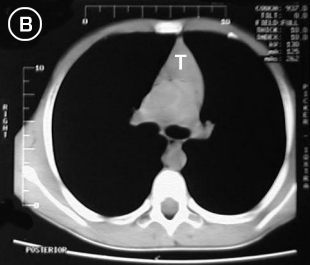

Tomografia A Tomografia B

Estudio tomografico milimetrico, progresivo desde el vértice hasta bases pulmonares, en donde no se apreciaron procesos pleuro-parenquimatosos; Mediastino sin adenopatías; En los cortes pretraqueales (A) y (B) se aprecia imagen de densidad de partes blandas en correlacion con probable timo hiperplasico y/o timoma, extendiendose distalmente anterior a los grandes vasos (C), observese su ausencia en el corte precordial inferior (D), donde apreciamos una silueta cardiaca de morfologia conservada, las bases pulmonares y el hemi-abdomen superior no mostraron alteraciones.

Tomografia C Tomografia D